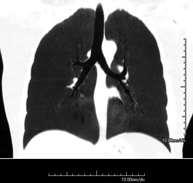

- Tórax- TC Tórax Prueba diagnóstica que consiste en obtener imágenes del tórax de alta definición anatómica (pulmones, corazón, mediastino, grandes vasos, caja torácica, etc.) mediante el empleo de un equipo de TC (Tomografía Computarizada). Dichas imágenes se estudian posteriormente en una estación de trabajo que permite reconstrucciones bidimendionales en diferentes planos del espacio y también reconstrucciones 3D (volumétricas). Algunos estudios requieren el empleo de contraste yodado para mejorar la definición de las imágenes. Prueba diagnóstica que consiste en obtener imágenes del tórax de alta definición anatómica (pulmones, corazón, mediastino, grandes vasos, caja torácica, etc.) mediante el empleo de un equipo de TC (Tomografía Computarizada). Dichas imágenes se estudian posteriormente en una estación de trabajo que permite reconstrucciones bidimendionales en diferentes planos del espacio y también reconstrucciones 3D (volumétricas). Algunos estudios requieren el empleo de contraste yodado para mejorar la definición de las imágenes.

- Angio-TC Arterias pulmonares (Estudio TEP, Tromboembolismo Pulmonar) Prueba diagnóstica que consiste en el estudio de las arterias pulmonares mediante el empleo de un equipo de TC (Tomografía Computarizada) obteniendo imágenes bi y tridimensionales. En este estudio es imprescindible el uso de contraste yodado, el cual permitirá una mejor definición anatómica. Esta prueba está principalmente indicada en los casos de sospecha de tromboembolismo pulmonar (TEP) para descartar o confirmar la presencia de coágulos sanguíneos en el interior de las arterias. Prueba diagnóstica que consiste en el estudio de las arterias pulmonares mediante el empleo de un equipo de TC (Tomografía Computarizada) obteniendo imágenes bi y tridimensionales. En este estudio es imprescindible el uso de contraste yodado, el cual permitirá una mejor definición anatómica. Esta prueba está principalmente indicada en los casos de sospecha de tromboembolismo pulmonar (TEP) para descartar o confirmar la presencia de coágulos sanguíneos en el interior de las arterias.

- TC Tórax alta resolución Prueba diagnóstica que consiste en el estudio del pulmón mediante el empleo de un equipo de TC (Tomografía Computarizada) obteniendo imágenes bi y tridimensionales que permiten un estudio anatómico altamente específico del pulmón, pudiendo valorar estructuras anatómicas de tamaño muy pequeño. Es una técnica muy importante en el estudio de los pacientes con sospecha de enfermedad pulmonar. Prueba diagnóstica que consiste en el estudio del pulmón mediante el empleo de un equipo de TC (Tomografía Computarizada) obteniendo imágenes bi y tridimensionales que permiten un estudio anatómico altamente específico del pulmón, pudiendo valorar estructuras anatómicas de tamaño muy pequeño. Es una técnica muy importante en el estudio de los pacientes con sospecha de enfermedad pulmonar.